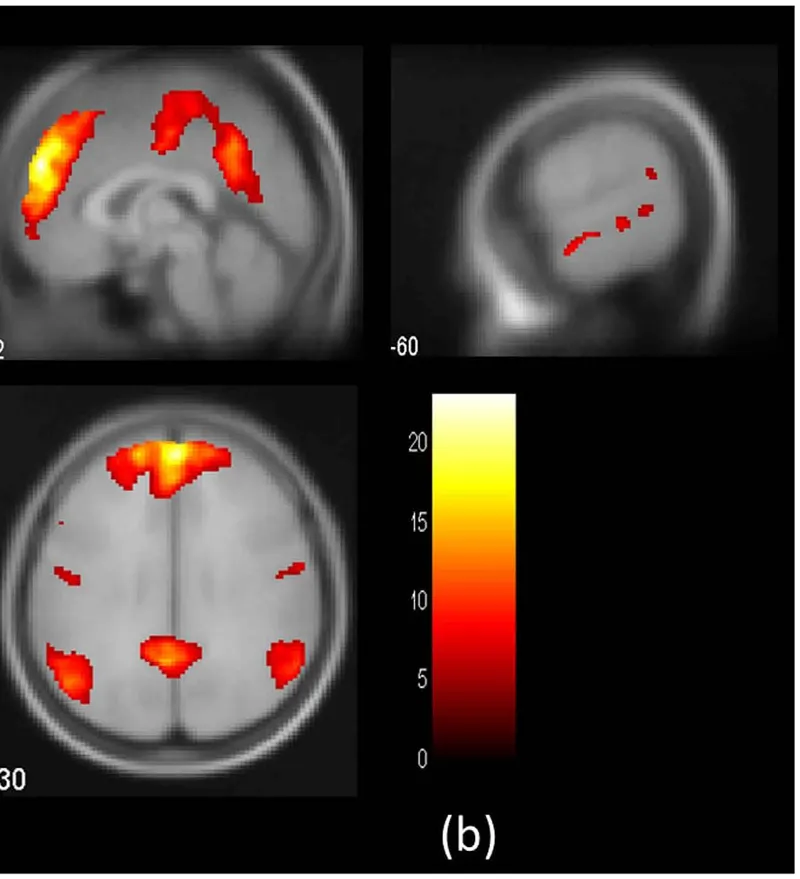

• The brain's pain-empathy network encodes outcome severity and drives blame, but is recruited differently for acceptability judgments – a neural dissociation between two outwardly similar moral responses

• Individuals who incur costly personal sacrifices to rescue others in a virtual emergency have larger right anterior insula – a region central to empathic motivation